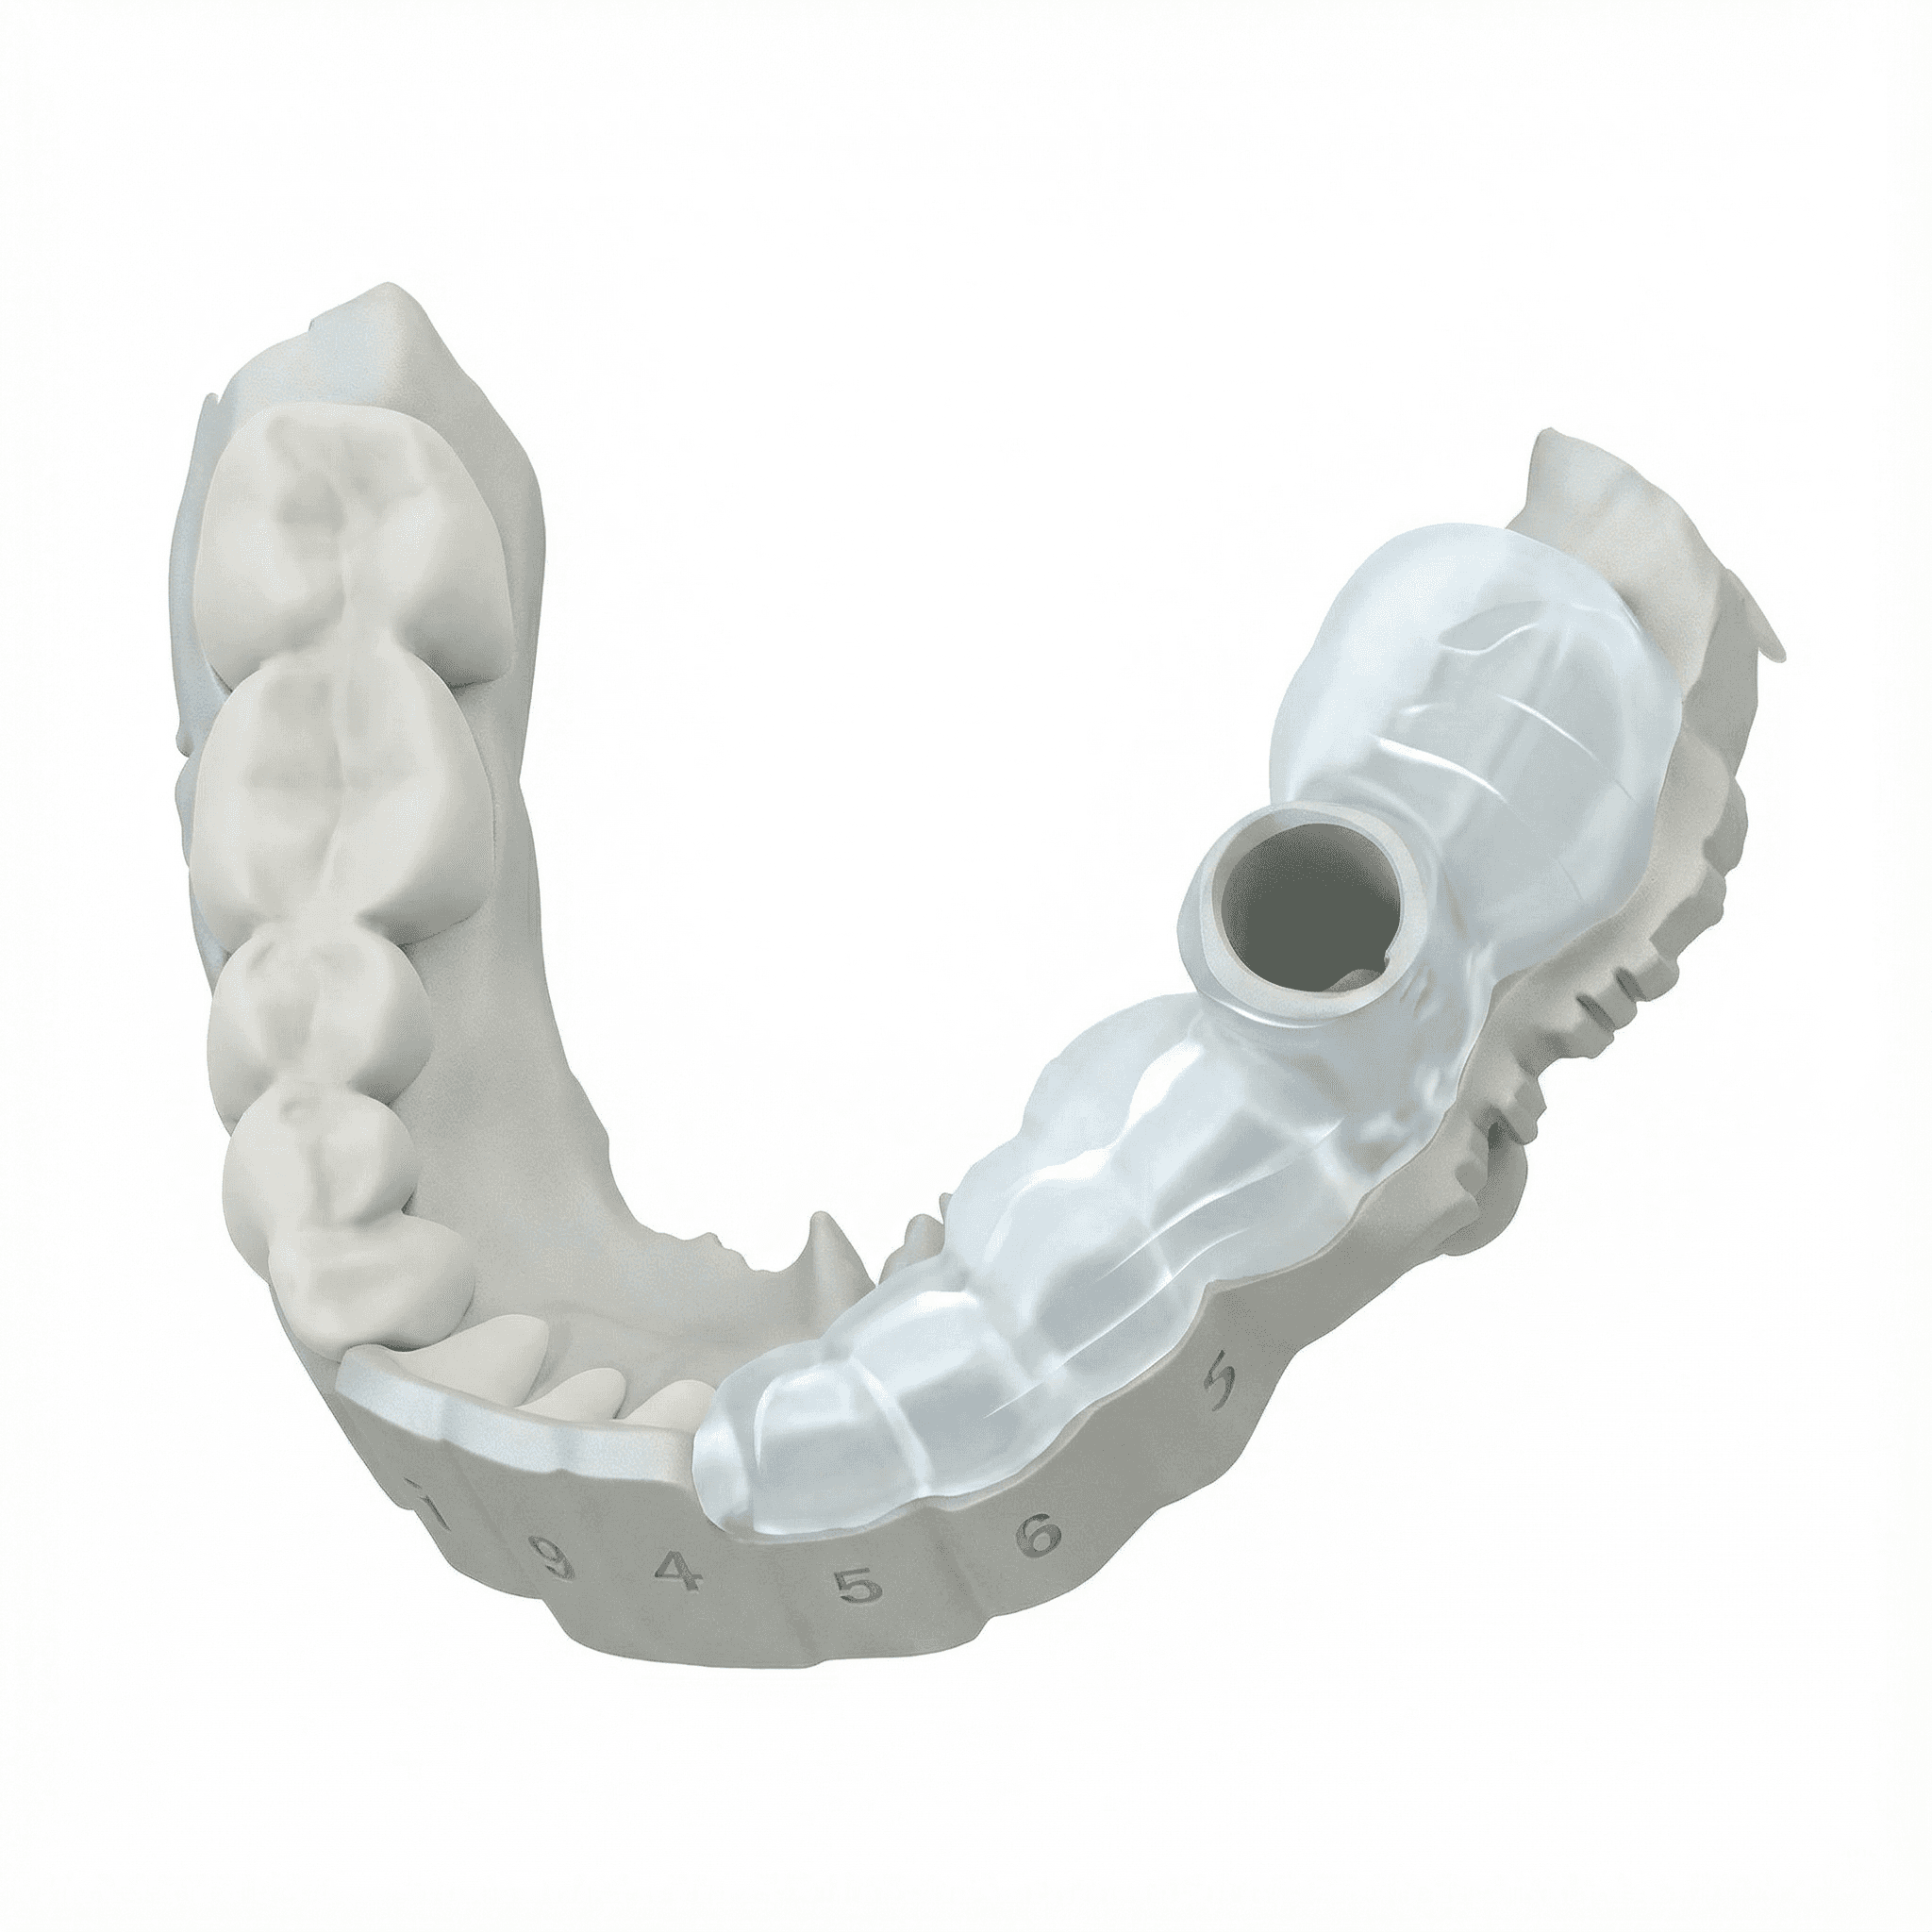

Sleeve & Drill Protocol Mapping

Sleeves, depths, and offsets calculated and verified the moment your implant is placed.

Sleeve auto-selected from library.

Verifies kit compatibility automatically.

Sleeve-Mapped Kits

Sleeves are auto placed at the exact implant's IPC level.